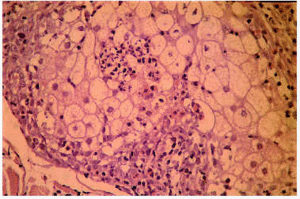

Desde el punto de vista histopatológico, en las etapas iniciales se observa espongiosis en la pared del infundíbulo folicular a expensas de un infiltrado de eosinófilos y células mononucleares. En etapas avanzadas del proceso se puede apreciar un auténtico clivaje o vesícula longitudinal, con neutrófilos, linfocitos y gran número de eosinófilos, que separa toda la pared infundibular (fig. 3) y afecta, con frecuencia, a la glándula sebácea (fig. 4)21. Algunas pústulas, primariamente intrafoliculares, se extienden secundariamente desde el infundíbulo hacia la epidermis vecina formando pústulas epidérmicas subcórneas10. Es posible encontrar, además, algún grado de degeneración mucinosa de la vaina epitelial externa22, 23.

Fig. 3.--Foliculitis pustulosa eosinofílica: absceso infundibular.

Fig. 4.--Foliculitis pustulosa eosinofílica: infiltración eosinofílica de la glándula sebácea.